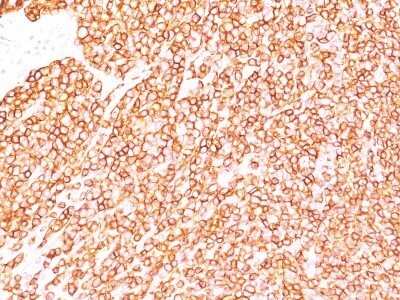

Immunohistochemistry-Paraffin: CD45RB Antibody (SPM569) - IHC-Prediluted [NBP2-44856] - Formalin-fixed, paraffin-embedded human lymphoma stained with CD45RB Monoclonal Antibody (SPM569)